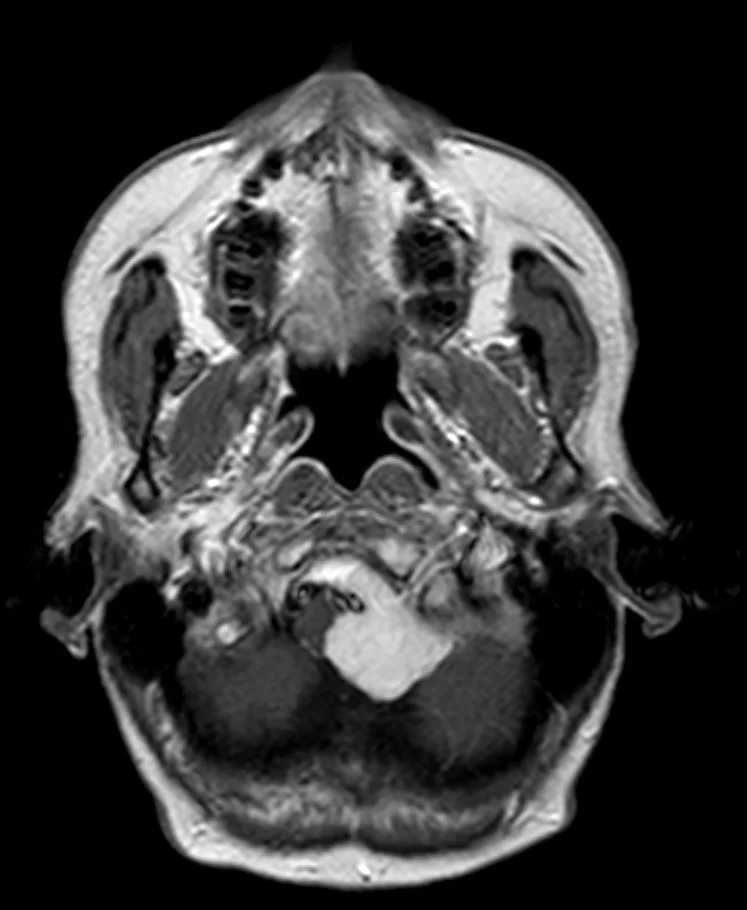

Ακουστικό Νευρίνωμα αριστερά

Ασθενής άνδρας, 52 ετών με κώφωση αριστερά και ιλιγγική συνδρομή. Η μαγνητική τομογραφία εγκεφάλου ανέδειξε χωροκατακτητική εξεργασία στην αριστερή γεφυροπαρεγκεφαλιδική